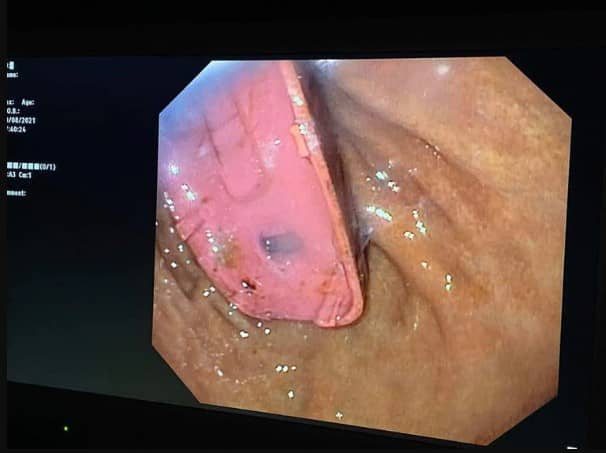

Afortunadamente, la cirugía se desarrolló sin problemas y el médico sacó el teléfono de su estómago. Telaku publicó en facebook fotos del teléfono, así como radiografías e imágenes endoscópicas. Estaba dentro del estómago del hombre.

En las fotos se puede apreciar al médico y su equipo ubicando y recuperando el teléfono del estómago, una operación que tardó dos horas hasta que retiraron el dispositivo.